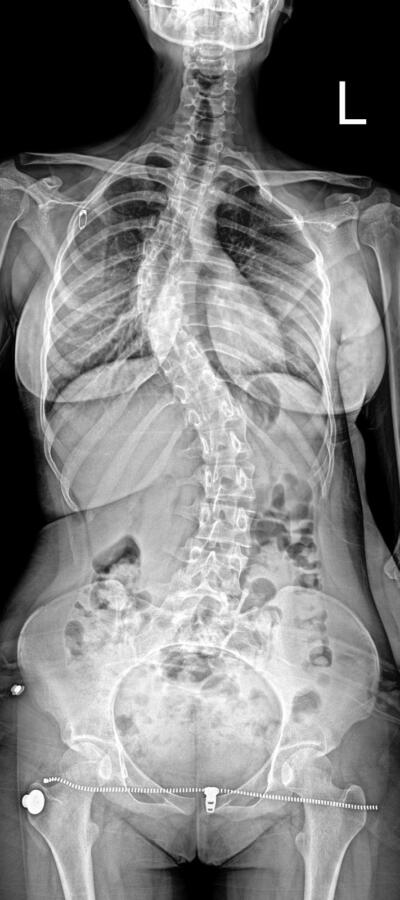

Omurganın sağa veya sola eğrilmesi sonucu ortaya çıkan skolyoz hastalığı, çocukluk ve ergenlik dönemlerinde sıkça görülürken, yetişkinlerde de ortaya çıkabiliyor. Bu rahatsızlıkla mücadele eden Türkiye’nin dört bir yanındaki vatandaşların Bolu Abant İzzet Baysal Üniversitesi Eğitim ve Araştırma Hastanesi’ne tedavi olmak için geldiğini belirten Ortopedi Klinik Sorumlusu Prof. Dr. Cengiz Işık, tedavi olanların tavsiyesi üzerine 81 ilden hasta geldiğini ifade etti. Tedavi esnasında öncelikli gayelerinin hastalığın ilerlemesini önlemek olduğunu belirten Işık, “Tedavi yöntemlerinin en büyüğü, en önemlisi ve en çok yapılanı da mümkün oldukça hastaya koruyucu hekimlik yapmak. Cerrahi müdahaleden önce hastalığın önlenmesini sağlamak” dedi.

Tavsiye üzerine Türkiye’nin 81 ilinden hasta geldiğini ifade eden Işık, “Omurgada oluşan skolyozun tedavisinde birçok tedavi yöntemi var. Tedavi yöntemlerinin en büyüğü, en önemlisi ve en çok yapılanı da mümkün oldukça hastaya koruyucu hekimlik yapmak. Cerrahi müdahaleden önce hastalığın önlenmesini sağlamak. Biz daha çok mümkün oldukça nasıl ilerlemesini durdurabileceğimiz, nasıl yavaşlatabileceğimizle uğraşıyoruz. Yılda ortalama 150-200 civarında omurga cerrahisi yapıyoruz. En çok gelen kısım Batı Karadeniz bölgesi; Bartın, Zonguldak, Karabük, Düzce, Bilecik gibi iller. Batı Karadeniz’de tekiz. Sadece Batı Karadeniz değil, Antalya’dan, Manisa’dan, Van’dan gelen de var. Bugün gelen hastalardan bir tanesi mesela Adana’dan gelmiş. Birkaç ay önce ameliyat ettiğimiz hasta da var. Bursa, İstanbul, Ankara’dan gelen de oluyor, tabii her yerden hasta geliyor. En çok yoğunluk olarak söylediğimiz tabii ki Batı Karadeniz. Herhalde ikinci sırada da İstanbul olur. Çünkü İstanbul’da tedaviye ulaşmak biraz daha zor olduğu için tedavi edilenlerin yakınları tarafından yönlendirilen kişiler oluyor bize” dedi.